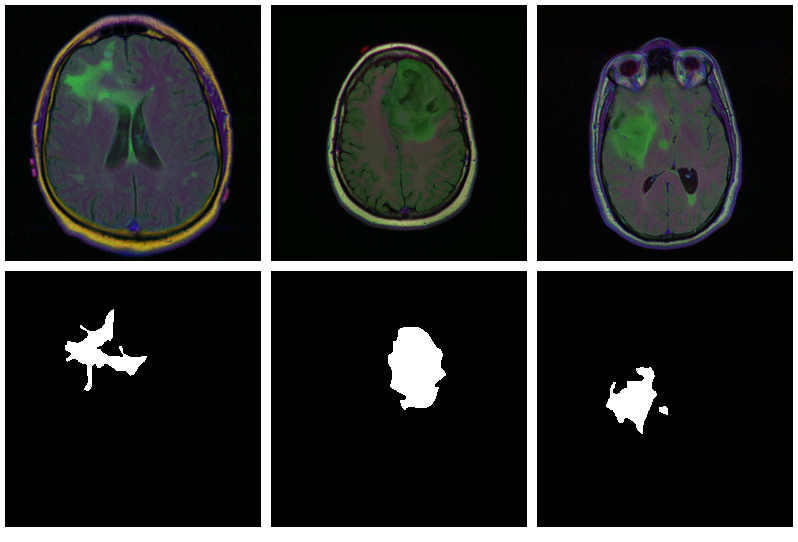

Here are three examples where the masks do indicate abnormalities:

Let’s see if we can build a U-Net that generates such masks for us.